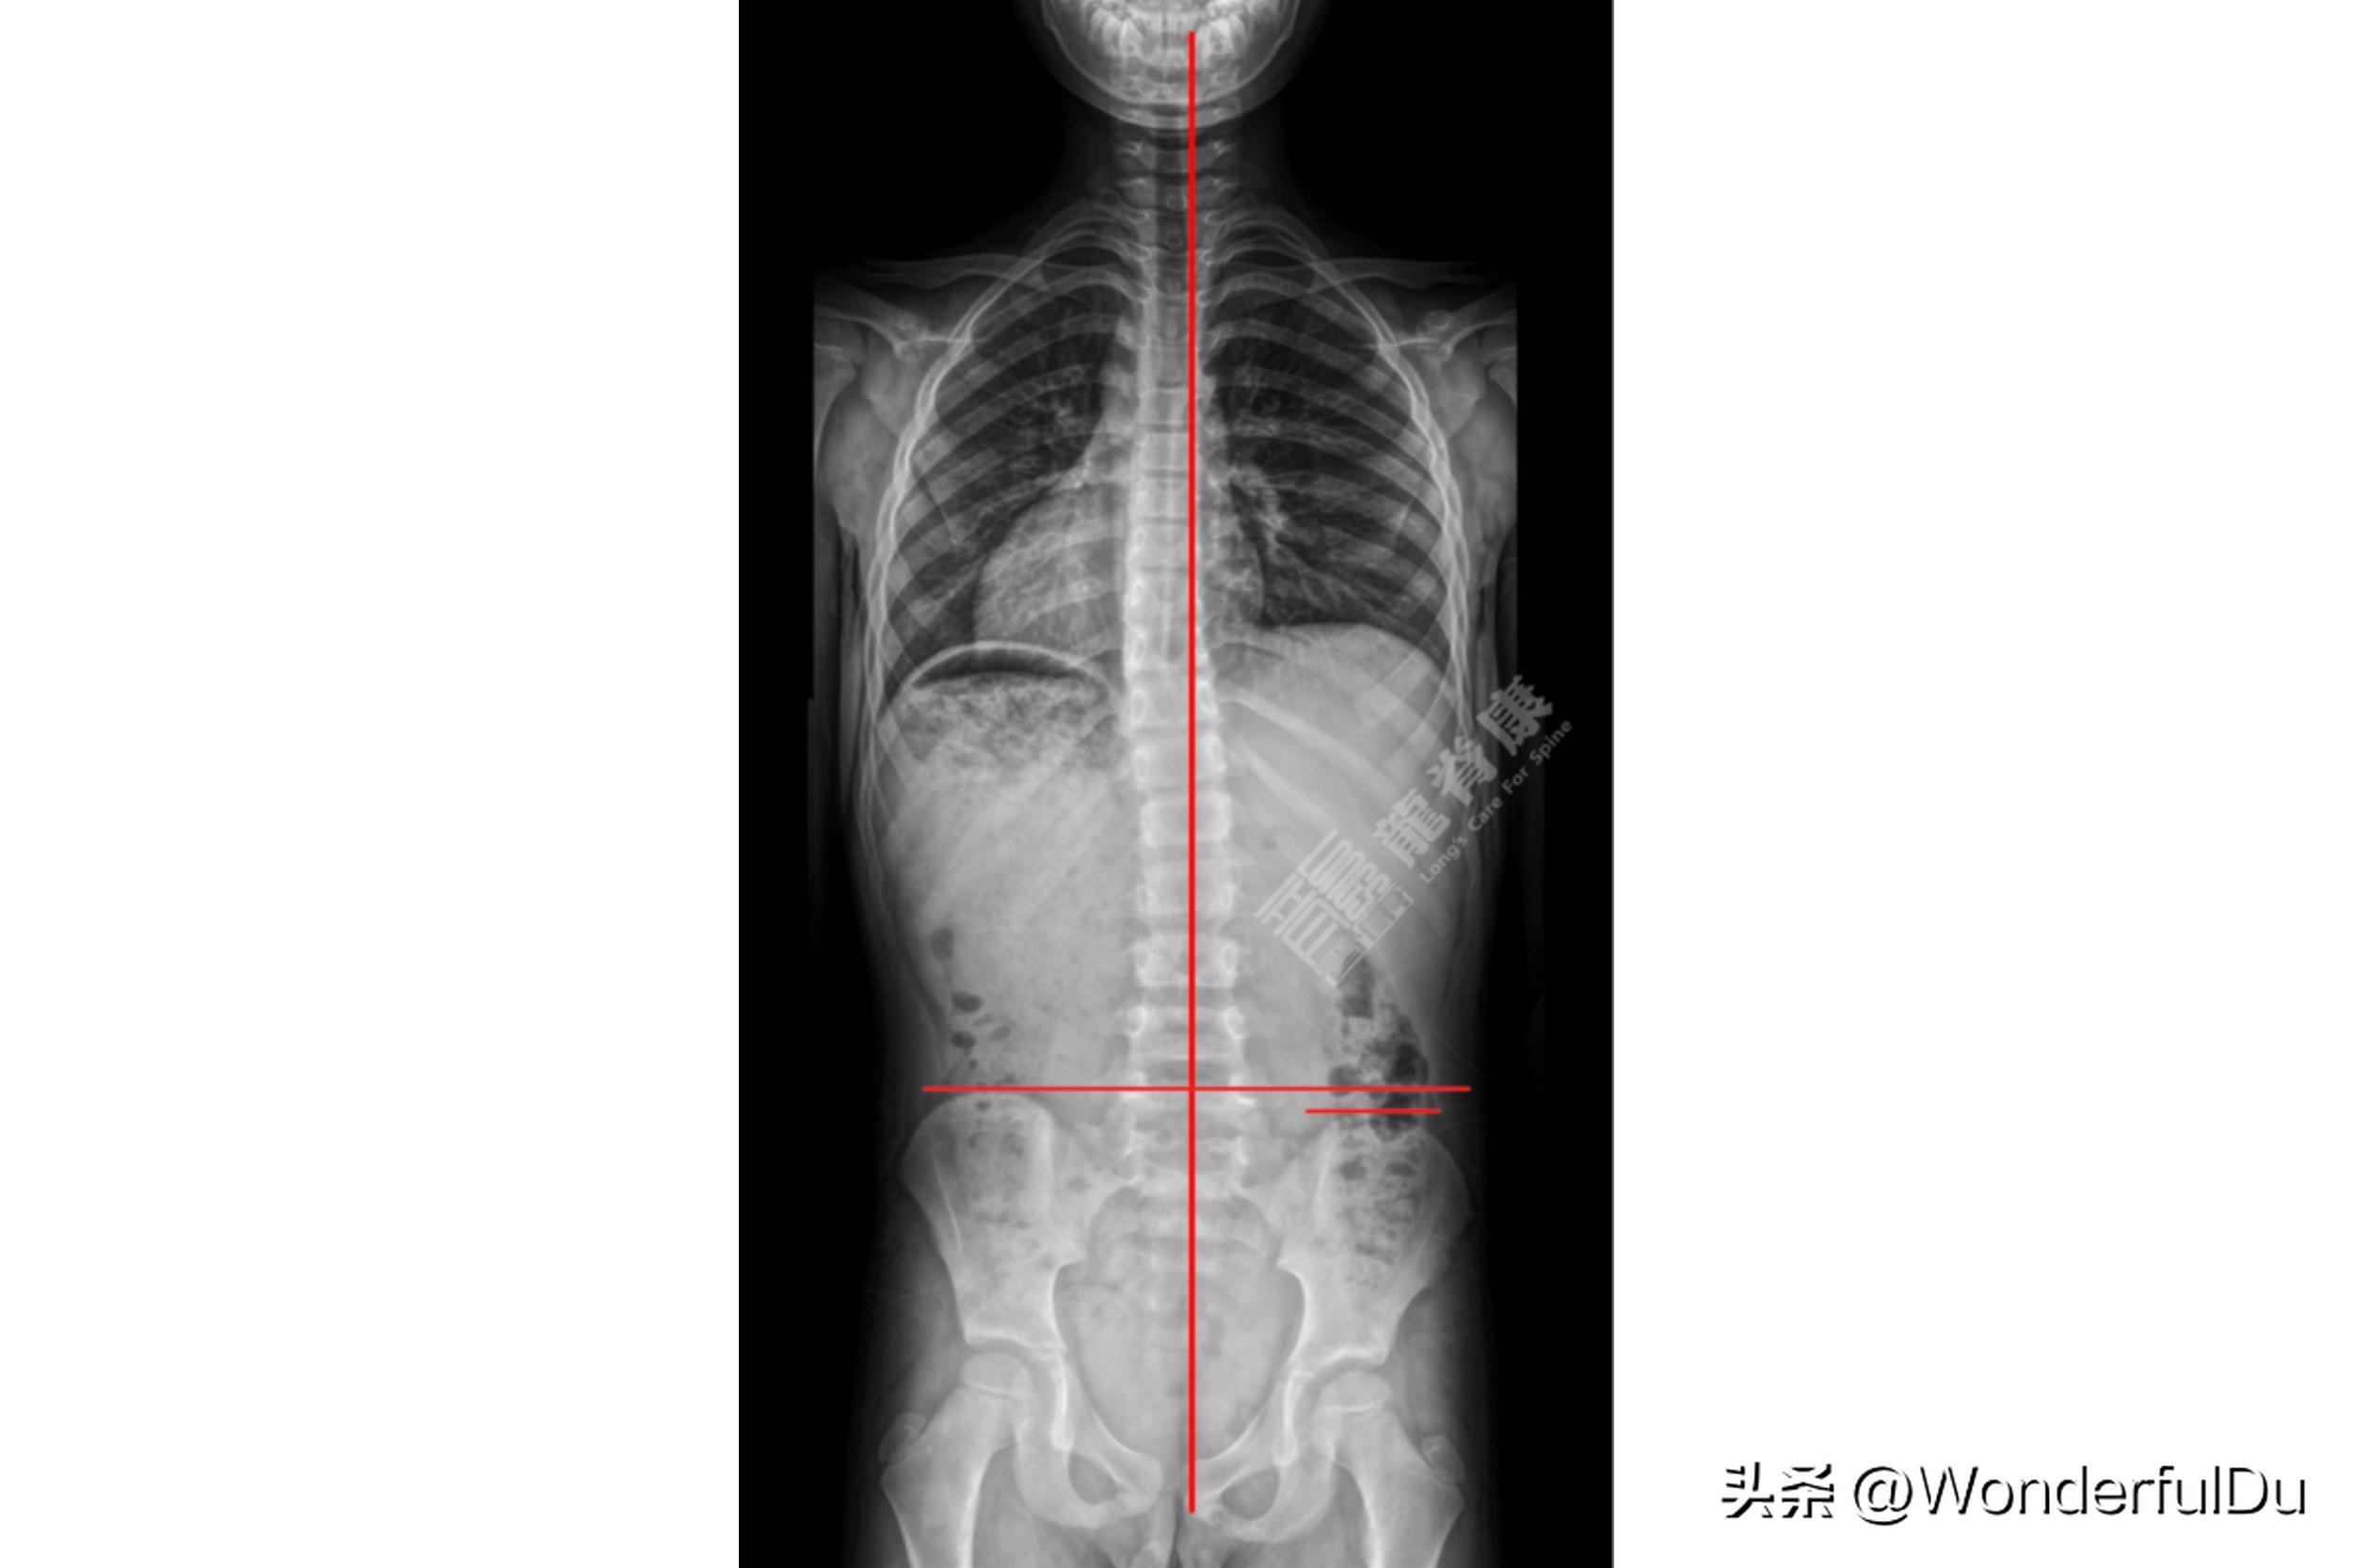

从x 光上可以看出小蓝 骨盆是不等高 的,其家长在2021.2.7去外院拍了全脊柱EOS成像(脱GBW支具 >12小时),提示:以T12-L1为中心向右侧凸,Cobb角约8°,胸腰交界向中线右偏移,Risser征:3-4级.

右下肢股骨长度38.8cm,胫骨长度为33.1cm,右下肢力线长度为72.2cm,解剖学长度为71.9cm。左下肢股骨长度39.5cm,胫骨长度为33.2cm,左下肢力线长度为73.1cm,解剖学长度为72.7cm。小蓝左下肢解剖学长度比右侧 高0.8cm ,为 真性长短脚 。

在站立或行走时,左下肢长,左侧骨盆会高于右侧,脊柱为了平衡,需往右侧凸,久而久之形成脊柱侧弯。针对此类侧弯,必须定制鞋垫,调节下肢力线,使骨盆稳定,而侧弯已经形成,同样需佩戴支具及加强训练。